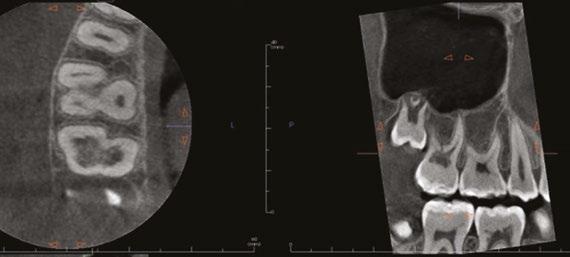

Figure 1: This CT reconstruction of the apical third of a premolar root shows the challenge we often encounter when negotiating root canals to their terminal lengths. In just these two canals, there are five potential impediments to passage of the first negotiating file to length